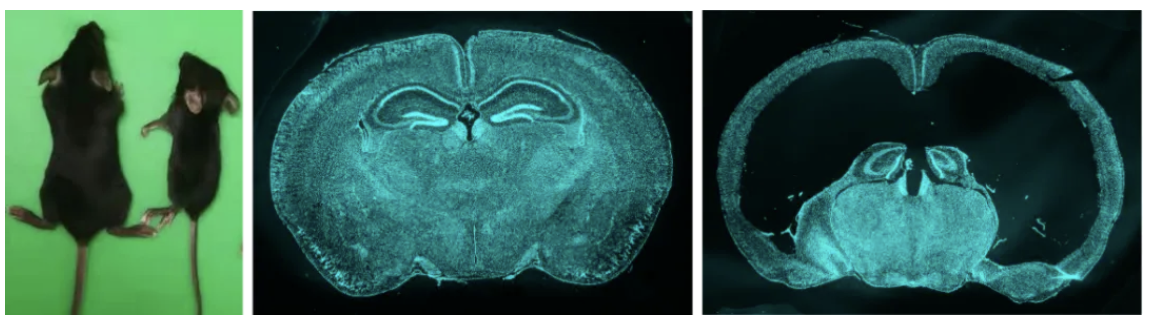

通过将Sspo-Cre和Sspo-CreER与DTA小鼠进行杂交,研究者们成功去除了子代小鼠的部分或者绝大部分SCO细胞。研究团队发现,当小鼠缺失SCO后,它们体型矮小,行动障碍,总体存活率很差。进一步发现,SCO缺陷小鼠的脑明显膨出,皮层很薄,局部皮层坍塌凹陷。脑切片显示,小鼠的脑室明显扩张,出现严重的大脑发育畸形。这些结果揭示SCO对大脑的生长发育是非常重要的,它是大脑生长发育不可或缺的一个重要器官(见图)。